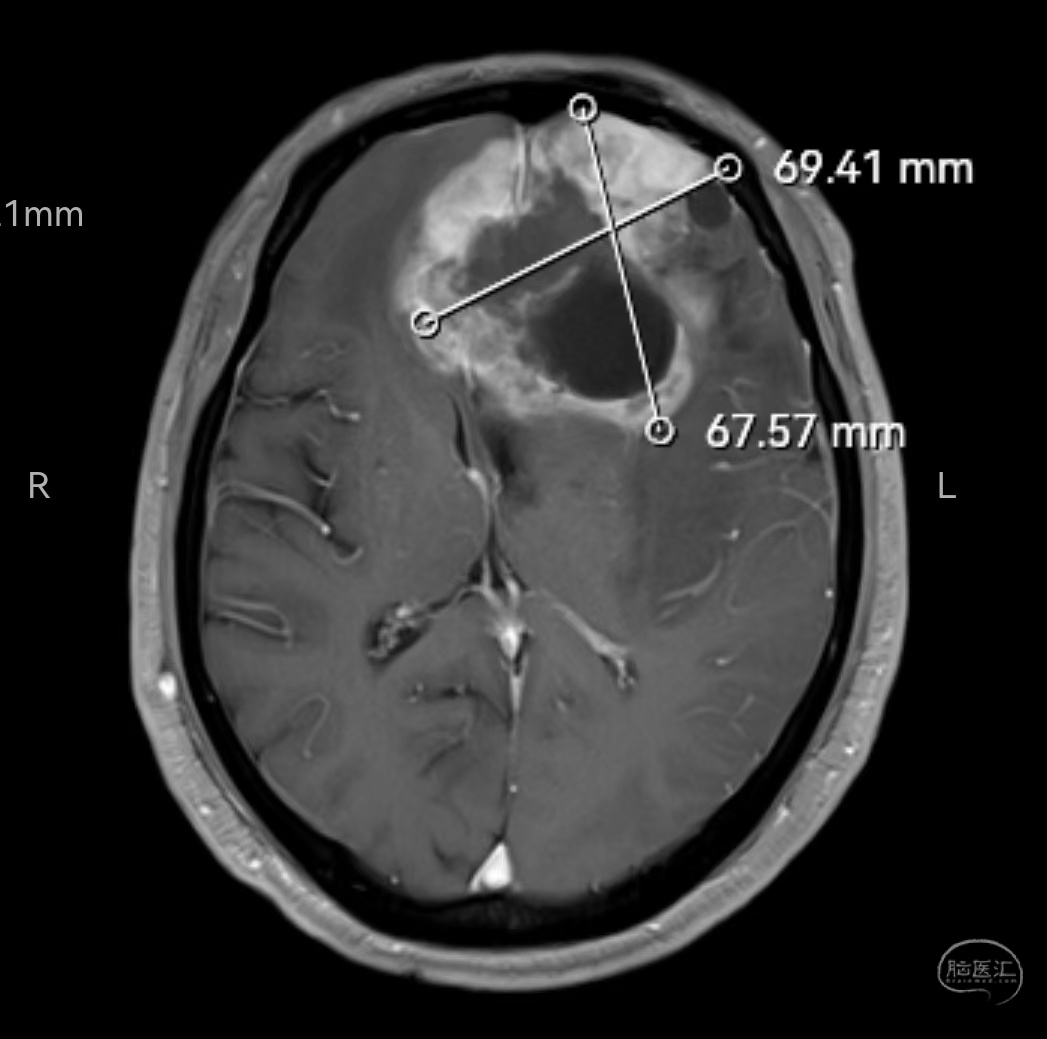

MRI增强轴位示肿瘤明显强化,位于双侧额叶,左侧为主,已侵犯至胼胝体嘴、膝部及左侧颞岛叶。肿瘤最大直径7厘米